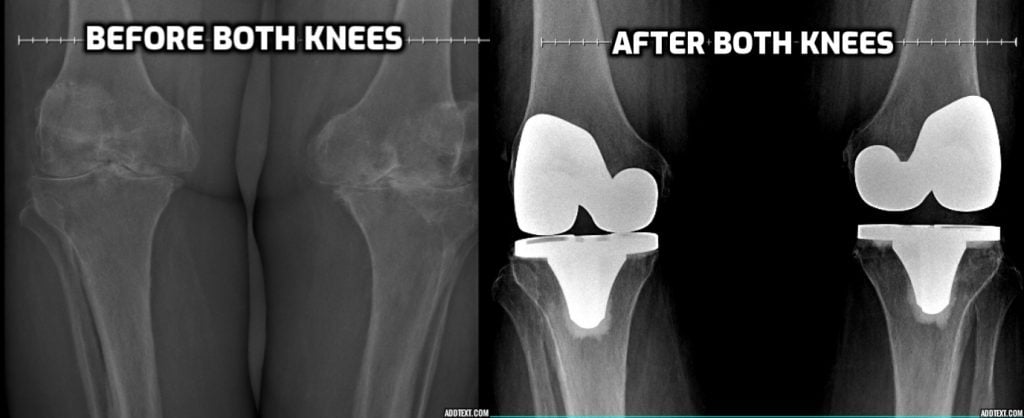

He and his team at HSS were outstanding. He and his team performed a miracle replacing my left knee which was an exceedingly difficult procedure. It went so well, and I was so confident in him that within 3 months he replaced my right knee as well.